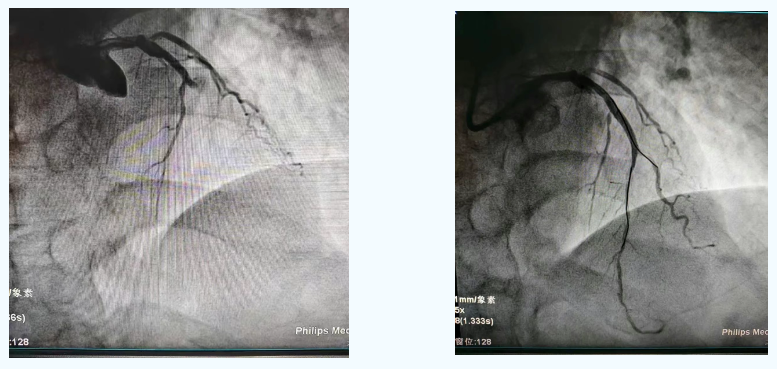

心血管科主任医师李爱勇综合评判后立即行急诊冠脉造影。造影结果显示,梁先生心脏的三条主要血管中,前降支100%完全闭塞,回旋支100%完全闭塞,右冠状动脉也有50%狭窄,病情复杂极其危重。

李爱勇迅速锁定导致此次心梗的“罪犯血管”——前降支。精准操作下,闭塞的血管被成功开通,一枚救命的支架稳稳植入。随着血流恢复,梁先生胸痛迅速消失,转危为安。